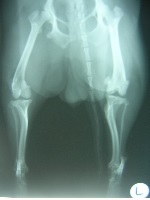

前十字靭帯断裂 ひざにある前十字靭帯(大腿骨とすねの骨をつなぐ靭帯)が切れて、ひざに体重がかけられなくなる。痛みで歩きづらそうに後ろ足を上げたり、引きずったり、地上にちょっとだけ足をつけて歩くようになる。急性のものであれば多くの場合、数日で元通り歩けるようになる。しかし、慢性化すると、とくに運動後に足をひきずることが多くなる。また、骨関節炎(変形性関節症)をともなうこともある。 前十字靭帯断裂の原因 前十字靭帯断裂は、事故などで急激な圧力が加わることが原因となる。 また、老化による靭帯の脆弱化や、肥満による膝関節にかかる負担によって切れてしまう場合もある。4~5歳以下の大型犬に多い症状ですが、室内犬で肥満している小型犬にも最近では多くなっている。 治療 ワンちゃんの症状や靱帯の状態、体重、運動量、飼い主の希望などによっても治療法は異なりますが、一般的には、内科的治療と外科的治療があります。 ●内科的治療 鎮痛剤の投与などによる痛みの管理、運動制限、肥満を防ぐための体重管理などを行います。内科的治療で症状が緩和され、良好な生活を送れるケースもありますが、症状が重度な場合や内科的治療を行って症状の改善がみられない場合などは、外科的治療を行います。 ●外科的治療 前十字靭帯断裂の手術方法にはさまざまな方法があり、筋膜を用いて靱帯を再建する方法、他の靭帯や人工靭帯で前十字靭帯を代用する方法や、骨を関節が安定する形に切除する方法(TTA、TPLO)などが知られています。ワンちゃんの症状や靱帯の状態などによって、適応時期や手術方法が異なります。 上の写真は先日手術した柴犬の女の子です。 関節の触診検査で診断し、手術を行いました。写真は関節内の前十字靭帯が切れている状態を写しています。関節内の靭帯の断端を処理し、半月板をチェックしました。 関節の安定化は関節内法(筋膜利用)と関節外法(人工靭帯)を併用しました。